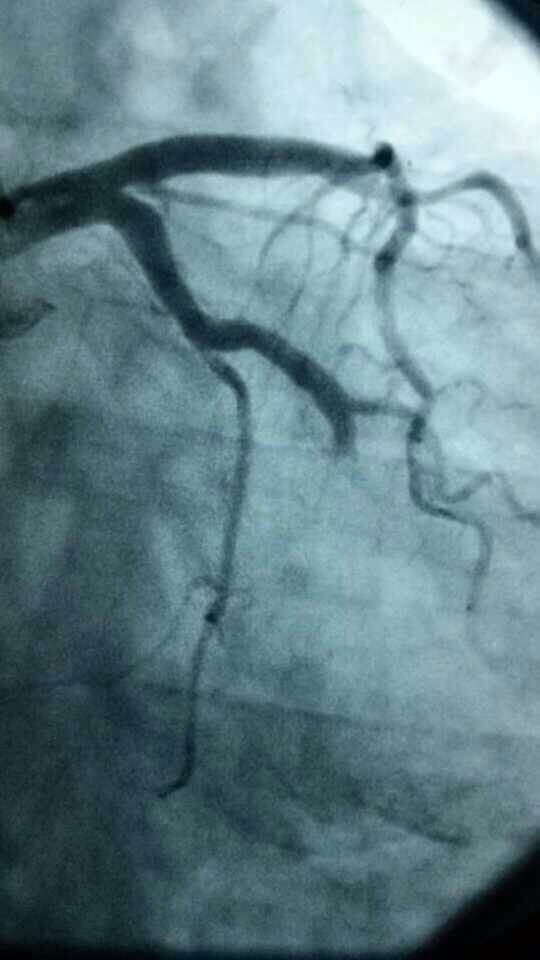

心内科8个小时成功抢救3名心梗患者

心内科医务人员在崔勇主任的带领下,蔡亚滨、林福根、雷建林、陈明辉、何晓、李仲伟等抢救团队连续奋战 8个小时成功抢救3名心梗患者。虽然工作艰辛,但接诊的三位病人都能转危为安,对医生来讲是最大的安慰。